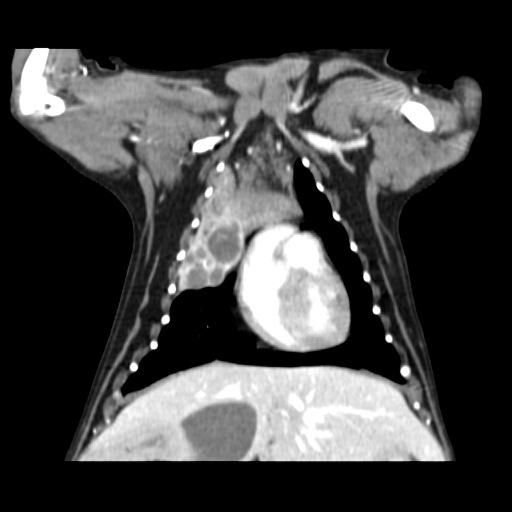

강아지 폐 종양 기수(진행 현황)에 대해 궁금합니다

엑스레이와 CT를 보았을 때, 강아지 폐암이 몇 달 정도 진행된건지 알 수 있을까요?

약 2~3주간 기침, 가래 증상만 있던 상태입니다.

폐종양은 보통 아무증상없이 수개월~수년에 걸쳐 발생하는게 일반적이나 드문경우 수주에 걸쳐 하게 커지기 때문에 영상검사 결과만으로 발생 기간을 추정할 수 없습니다.